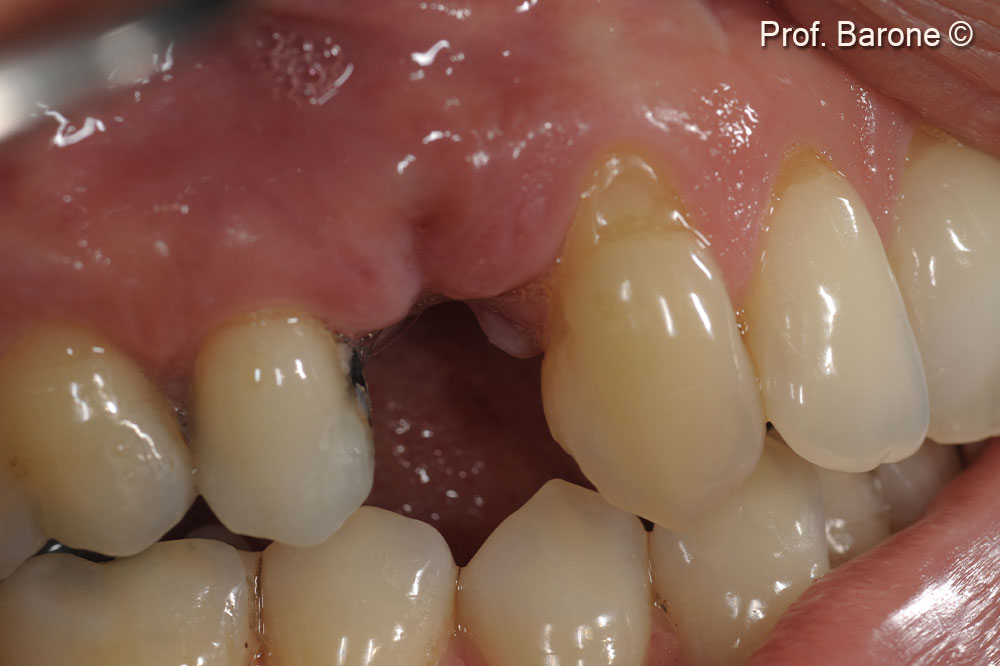

Clinical occlusal view 16 weeks after ridge preservation